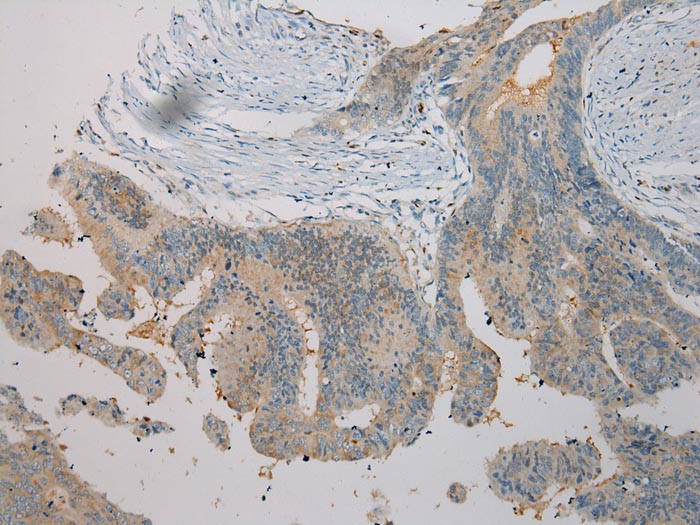

Immunohistochemical analysis of paraffin-embedded Human Cervical cancer tissue using #40258 at dilution 1/100.

Immunohistochemical analysis of paraffin-embedded Human Colorectal cancer tissue using #40258 at dilution 1/100.